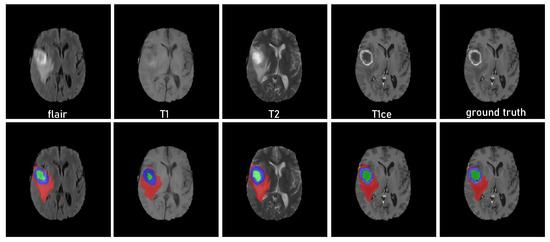

3.1. Dataset